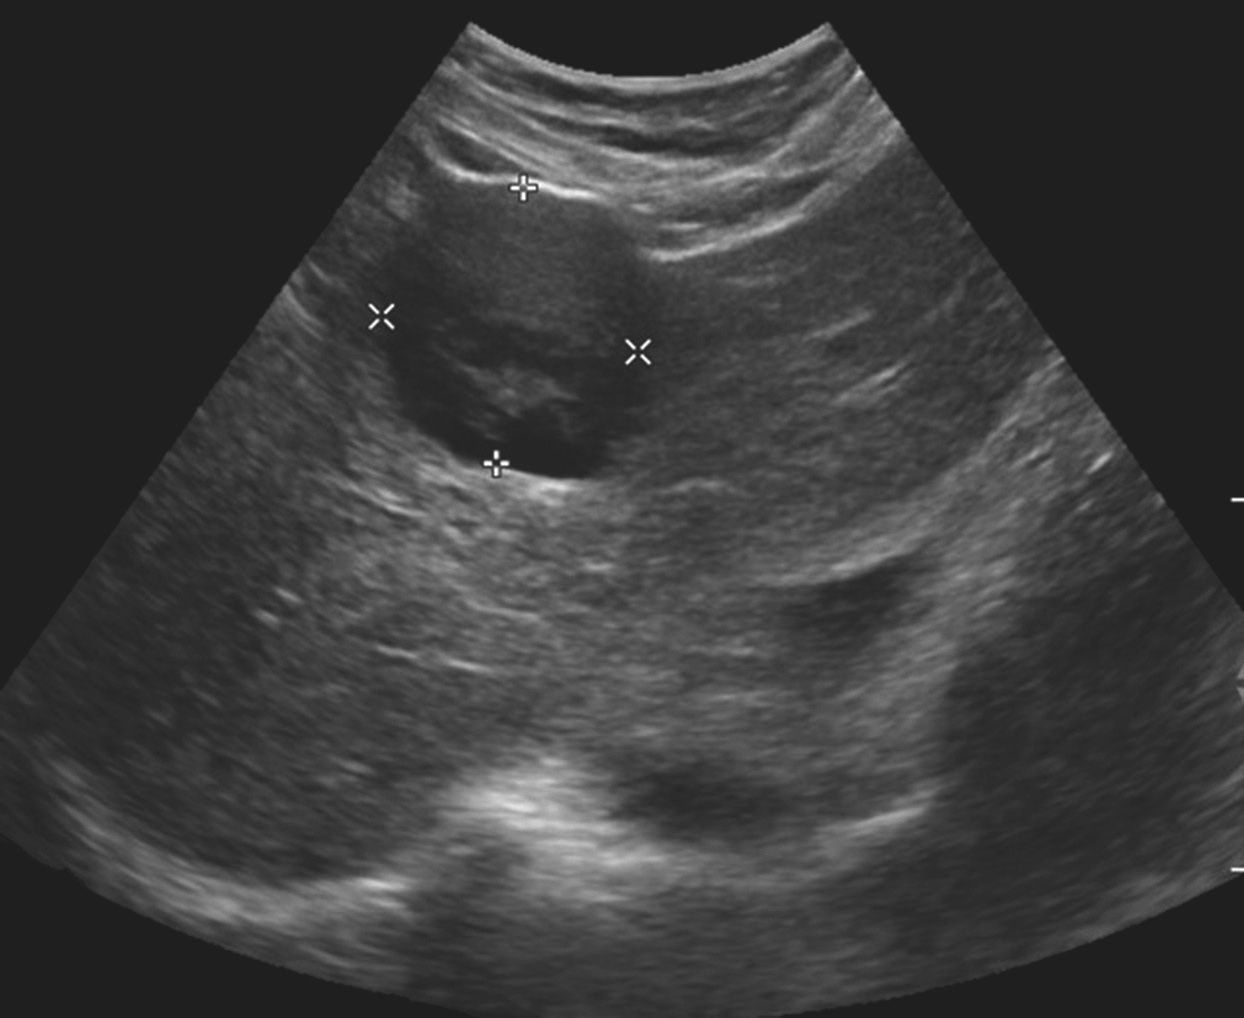

(2)形态:多数病变为形态规则的圆形、类圆形或不规则形团块,大多数癌结节具有完整的包膜,边界清楚,少数癌结节可无包膜,与周围组织界限不清(图1-7-1)。

图1-7-1 肝细胞癌灰阶超声图像

病灶呈低回声,内回声不均匀,向肝被膜外凸出